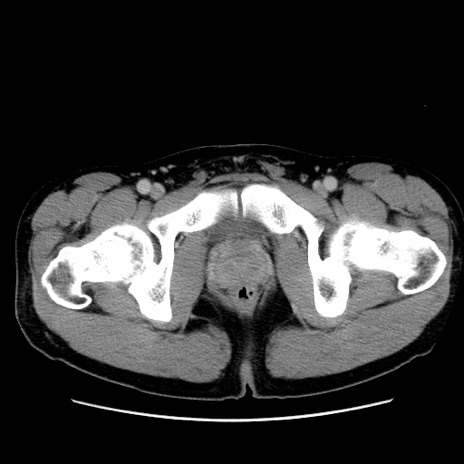

症例36(横断像)

【症例】20歳代 男性

【主訴】心窩部痛

【現病歴】今朝より上腹部痛あり。一旦軽快していたが再度出現したため救急要請。昨日夕に白身の魚を含む刺身を食べた。

【身体所見】BP 136/89mmHg、HR 74/min、BT 37.0℃、腹部:膨満、軟、心窩部に圧痛あり。反跳痛なし、筋性防御なし、腸雑音やや亢進あり。

【データ】WBC 17700、CRP 0.48